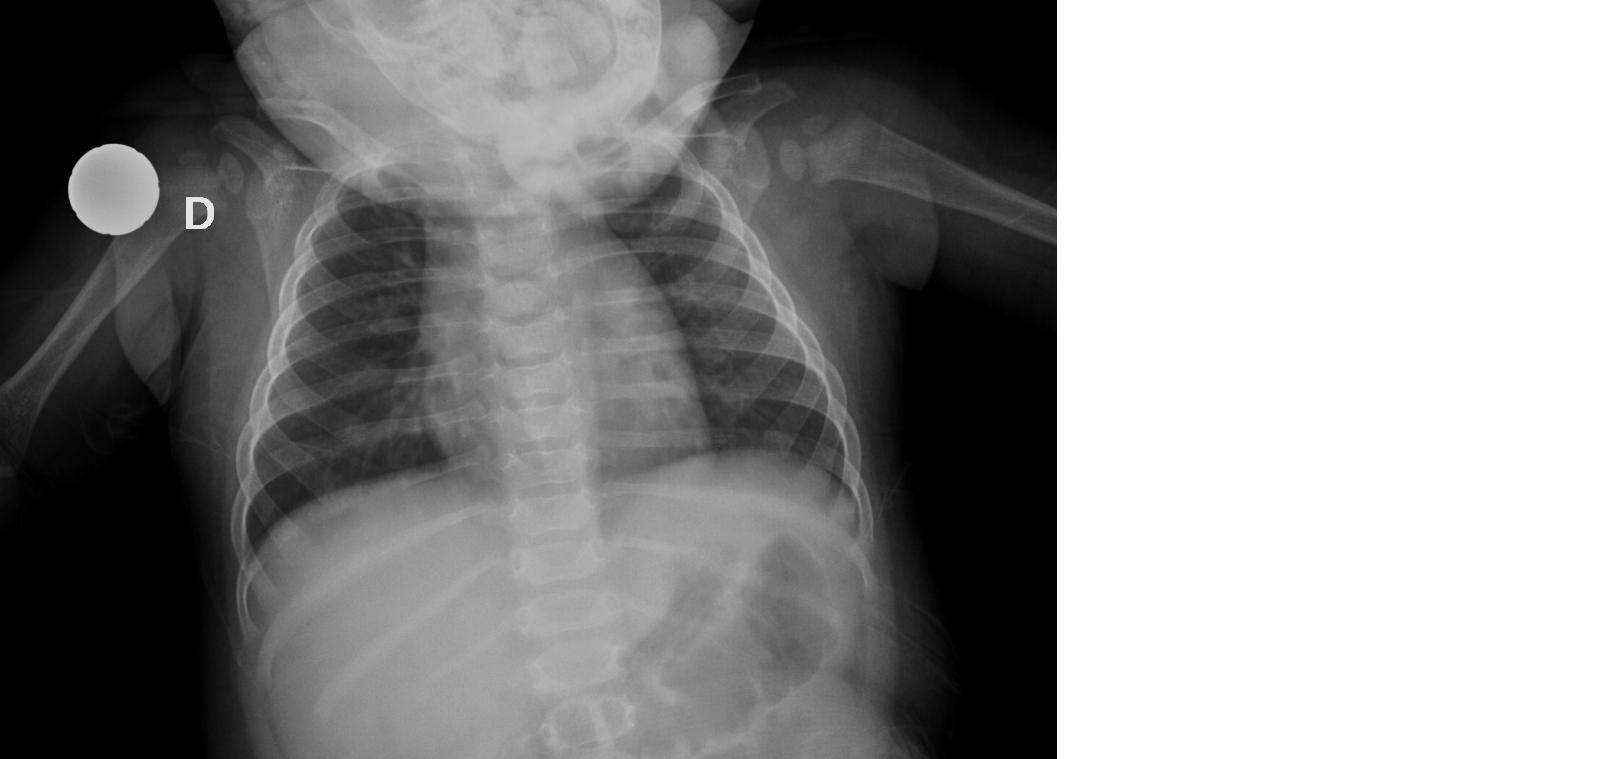

Giacomo, un bambino italiano di 8 mesi, giungeva alla nostra osservazione per febbre e difficolt� respiratoria ingravescente. Il bambino presentava condizioni generali lievemente scadute con dispnea (FR 64 atti/min, SatO2: 95%); all'auscultazione del torace si apprezzavano crepitii fini tele-inspiratori diffusi associati a gemiti espiratori ed inspiratori. L�Rx del torace (Figura 2) confermava, anche in questo caso, la diagnosi di bronchiolite. Gli esami ematici mostravano la presenza di valori di emoglobina ai limiti bassi della norma (Hb 10,8 g/dl) associati a MCV lievemente ridotto (68,7 fl) e reticolociti ai limiti bassi della norma (31.600/ul). All�anamnesi emergeva che il bambino, nato e cresciuto in Italia, era stato alimentato per 3 mesi con allattamento materno e successivamente con latte di capra (2 pasti/die) e latte di mandorla (1 pasto/die). Inoltre, non aveva ricevuto profilassi con vitamina D e la madre non aveva effettuato la supplementazione con vitamina D durante la gravidanza. Ulteriori esami ematici mostravano valori ridotti di ferritina (9 ng/ml) e di 25-drossivitamina-D (valori indosabili), associati ad iperparatiroidismo secondario (PTH 140 pg/ml). I valori di calcio, fosforo e fosfatasi alcalina risultavano nella norma e non erano evidenti segni clinici di rachitismo.

Figura 2.